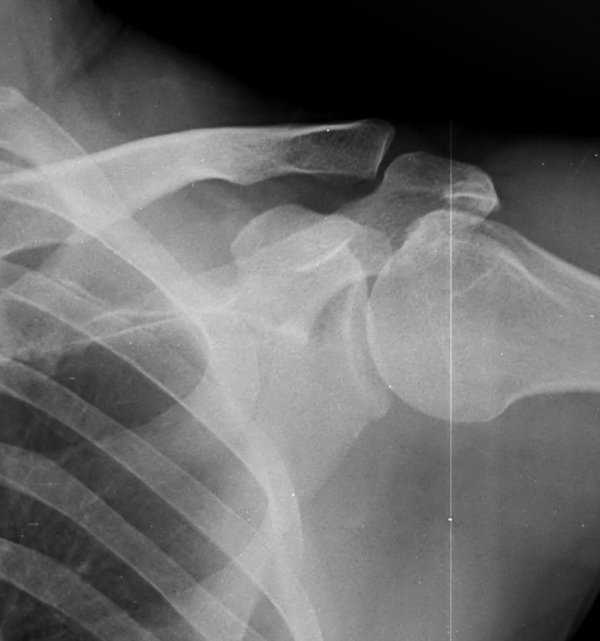

´Ü¼ø¹æ»ç¼±°Ë»ç

ƯÀÌ °ßºÀ ¾Æ·§¸éÀÇ °æÈ­ ¼Ò°ß ¹× °ßºÀ ¾Æ·¡ ¿¹¸®ÇÑ °ñ±ØÀÌ °üÂûµÊ

¹æ»ç¼±»çÁøÀ̳ª ÀÚ±â°ø¸í°Ë»ç¿¡¼­ °ñ±ØÀÌ °üÂûµÇ°í ±Ø»ó°Ç ÆÄ¿­ÀÌ ÀÖ´Â °æ¿ì °Ë»ç¿¡¼­ º¸ÀÌ´Â

°ñ±ØÀÌ ±Ø»ç°ÇÆÄ¿­ÀÇ ¿øÀÎÀ̶ó°í ÃßÁ¤ÇÒ ¼öµµ ÀÖ´Ù.  ±×·¯³ª ±Ø»ó°ÇÆÄ¿­ÀÌ Ç¥Ãþº¸´Ù´Â ½ÉÃþ¿¡¼­

´õ ¸¹ÀÌ ¹ß»ýÇϰí Áõ»óÀ» ÀÏÀ¸Å°Áö ¾Ê´Â °ñ±ØÀÌ ¸¹Àº Á¡À» °í·ÁÇÒ ¶§ °Ë»ç¿¡¼­ º¸ÀÌ´Â °ñ±ØÀ»

Ä¡·á(°ßºÀ¼ºÇü¼ú)ÀÇ ´ë»óÀ¸·Î ÇÏ´Â °ÍÀº Çϸ®ÀûÀÎ °áÁ¤ÀÌ ¾Æ´Ï´Ù. ÀÌ È¯ÀÚÀÇ °æ¿ìó·³ ±Ø»ó°Ç